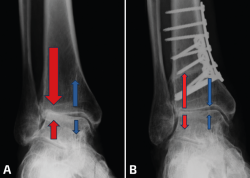

Hay que tener en cuenta que las intervenciones supramaleolares pueden ser suficientes, insuficientes o incluso cambiar una “adecuada” alineación previa del retropié en el proceso de buscar un nuevo equilibrio de las fuerzas de carga. Por esto, siempre hay que tener en consideración la necesidad de procedimientos inframaleolares. Más aún, existen situaciones en las cuales se podría considerar solo una intervención inframaleolar si el caso en particular lo permite. También se pueden identificar presentaciones atípicas de desaxación, aunque menos frecuentes en general, como lo son las deformidades en plano valgo con una interlínea de tobillo en varo. En estas situaciones las actuaciones supra- e inframaleolar serán de sentido inverso (Figura 3).

Figura 3. Malalineaminento en varo tobillo-valgo subtalar (osteotomía –OTT– supramaleolar –SM– de apertura más OTT de calcáneo varizante).